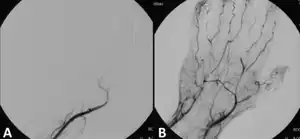

![]() Angiografie reprezentând o tromboză și situația după tratamentul fibrinolitic | |